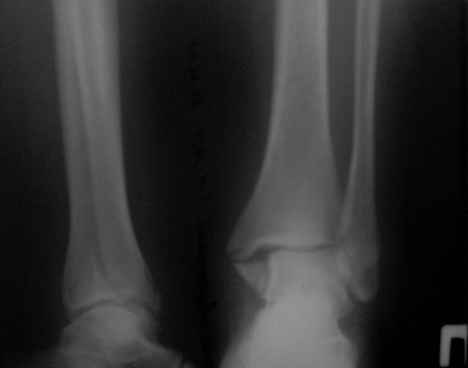

перелом лодыжек трёхмесячной давности

Здравствуйте, коллеги! Ко мне на консультацию обратилась больная 54 года, 110 кг весом.

Травма 3 мес. назад, лечилась амбулаторно в гипсовой лонгете. Как поступить далее? Я планирую ORIF, внутреннюю лодыжку - спицами и проволокой, наружную - пластиной 1\3 трубки. Позиционный винт для фиксации синдесмоза. Как Вы считаете, это верная тактика? какой вероятен исход? Какие имеются нюансы в этом сроке, особенности техники? Может стоит вначале разработать движения в голеностопе? Нужен ли гипс после операции ?С уважением Д.Б.

Правый снимок или размыт, или, что вероятнее - все срослось. Лечите деф. артроз, коллега. А металл, металл в металлолом. Или снимки более четкие. С уважением.

Снимки конечно нечитаемые. Оставлять так конечно нельзя, не устранен подвывих. Но нужно внимательно оченить зоны перелома, т.к. срок достаточно большой. Может так получиться, что вы пойдете на МОС, а найти зоны переломов будет очень сложно, придется отломки разъединять. Хотя в личной практике часто встречаю подобные переломы 2,3,4 мес давности, и когда открываешь - ВООБЩЕ нет признаков сращения, что мне пока непонятно. Если все таки нет сращения рекомендовал бы наружную пластиной с позиционным с концевой резьбой (или рассверлить fibula до ширины резьбы, обязательно зацепившись за внутренний кортикальный слой tibia), а внутреннюю конечно винтом, отломок позволяет. Но есть еще один момент, даже если нет сращения, то зона синдесмоза наверняка уже заполнена рубцовой тканью, поэтому просто затянуть его не получится, нужно или делать ревизию или вообще идти на ВКДО.

Прошу прощения за качество снимков . Во вторник постараюсь сбросить более читабельные снимки + мортиз проекцию . Спасибо за ответ . С уважением Д.Б.